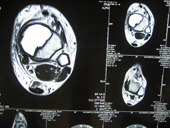

| Giant cell tumour MRI |

MRI2 |

MRI3 |